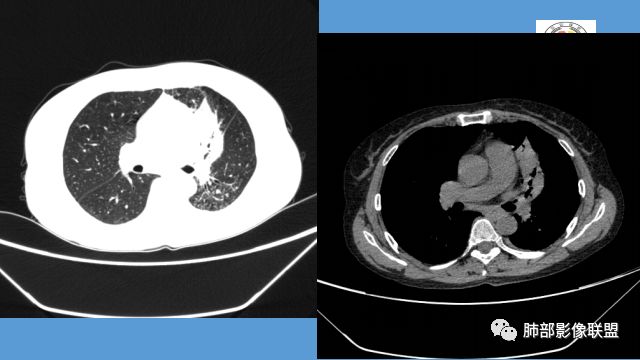

左肺团块影,形态不规则,其内见充气支气管征,增强扫描明显强化,其内见液化坏死区。下叶基底段见斑点状密度增高影。双肺门见斑点状钙化影。疾病谱有结核,增强除外了。肺癌和淋巴瘤鉴别。

病灶远端有扩张支气管,树芽,实变,纵隔肺内淋巴结钙化,考虑肺结核。

整个上叶尖后段阻塞性肺不张的表现,从强化来看没有异常结节状或肿块样强化,肿块内部点状钙化、纵隔多发小淋巴结、下叶背段有树芽征,整体来看支持肺结核,让人不放心的是最后一幅冠状位重建的图像尖后段支气管堵了,而且有轻度的隆起,所以很难除外粘液表皮样癌(女性,鳞癌可能性小),如果是我写报告肯定会建议纤支镜检查

中年女性,反复咳嗽咳痰4月,加重半月,咳嗽,咳黄痰。胸CT:左肺体积缩小,左肺上叶病变,病灶内可见支气管征,病灶边缘可见棘突样改变,病灶周围可见结节状卫星灶,纵隔可见淋巴结肿大,部分淋巴结可见钙化灶。增强CT病灶内可见低密度坏死区,冠状位病灶内支气管可见扩张,病灶整体呈收缩,考虑患者为良性慢性感染性病变,结核?放线?,建议支气管镜检查。

考虑结核伴混合感染。中青年女性,持续低热、不正规抗感染症状加重。左上肺低密度肿块,左上固有段支气管未显影(结核侵蚀干酪样坏死),左上舌段支气管通畅但增厚变形。左下肺树芽征新发支气管播散。鉴别:粘液腺癌

左上叶实变不张,膨胀生长,上叶开口阻塞?,病灶内支气管扩张,明显延迟强化,内见低密度灶及点状钙化,周边见小叶间隔增厚丶结节,右斜裂结节

中年女性,反复咳嗽咳痰4月。胸CT:左肺上叶块状病变,病灶内可见支气管征,边缘见棘突样改变,周围可见结节状卫星灶,纵隔可见淋巴结肿大,部分淋巴结可见钙化灶。增强CT病灶内可见低密度坏死区。病灶整体呈收缩,考虑为良性病变,结核可能性大,建议支气管镜检查。